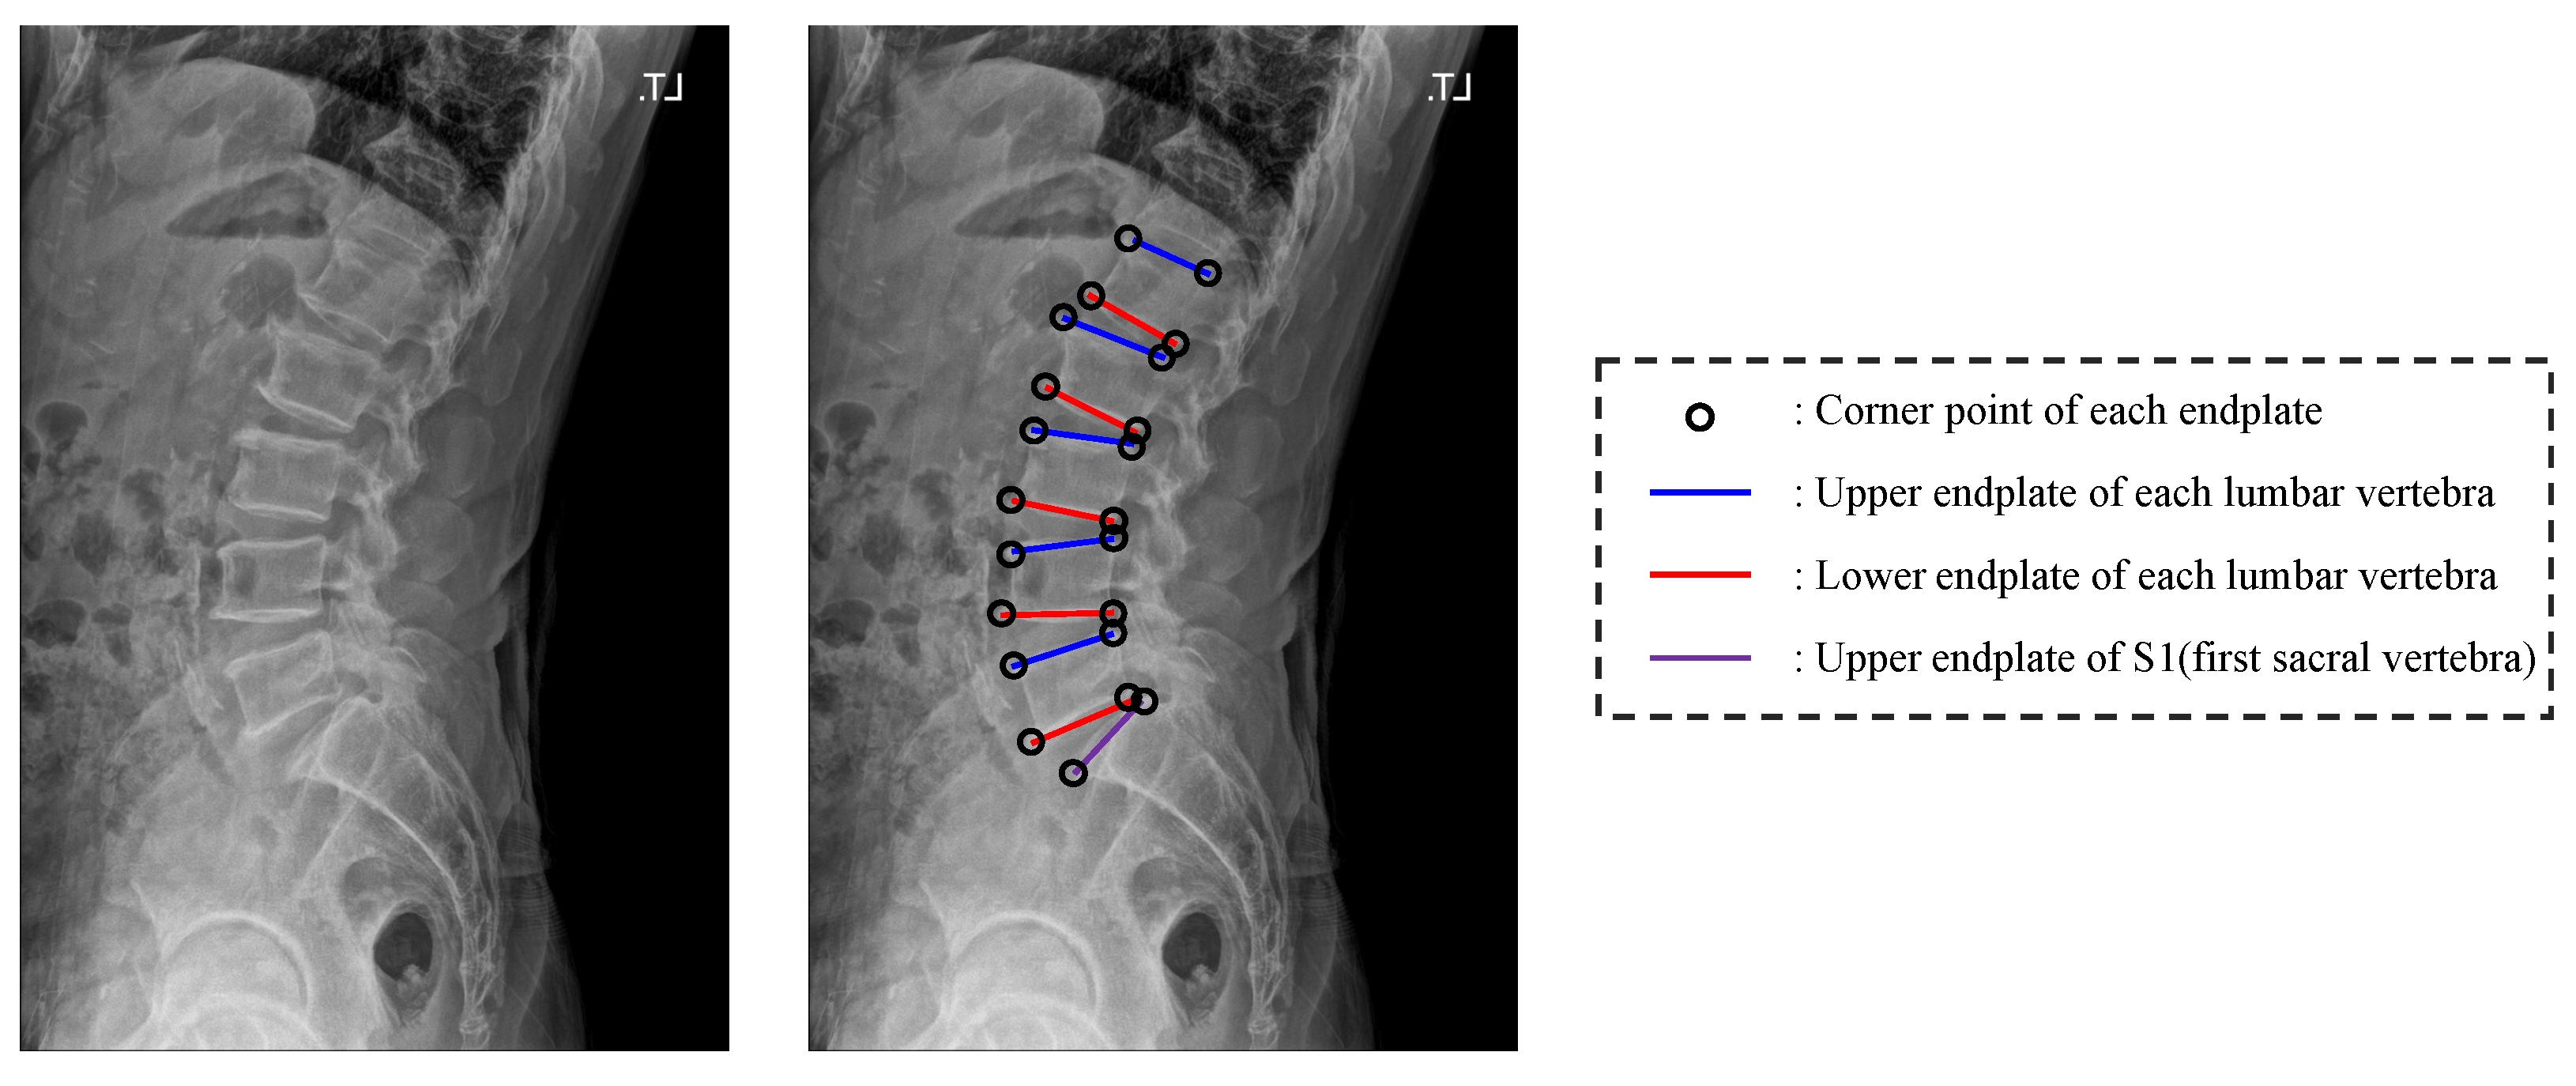

From www.researchgate.net